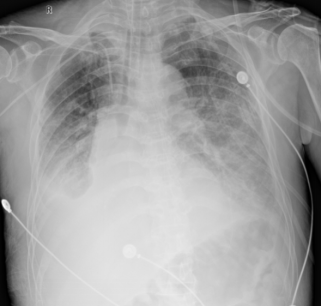

• 床旁胸片(2025-02-23):双肺渗出明显增加,且以双下肺为主(图8)

图片

8  患者床旁胸片(2025-02-23)